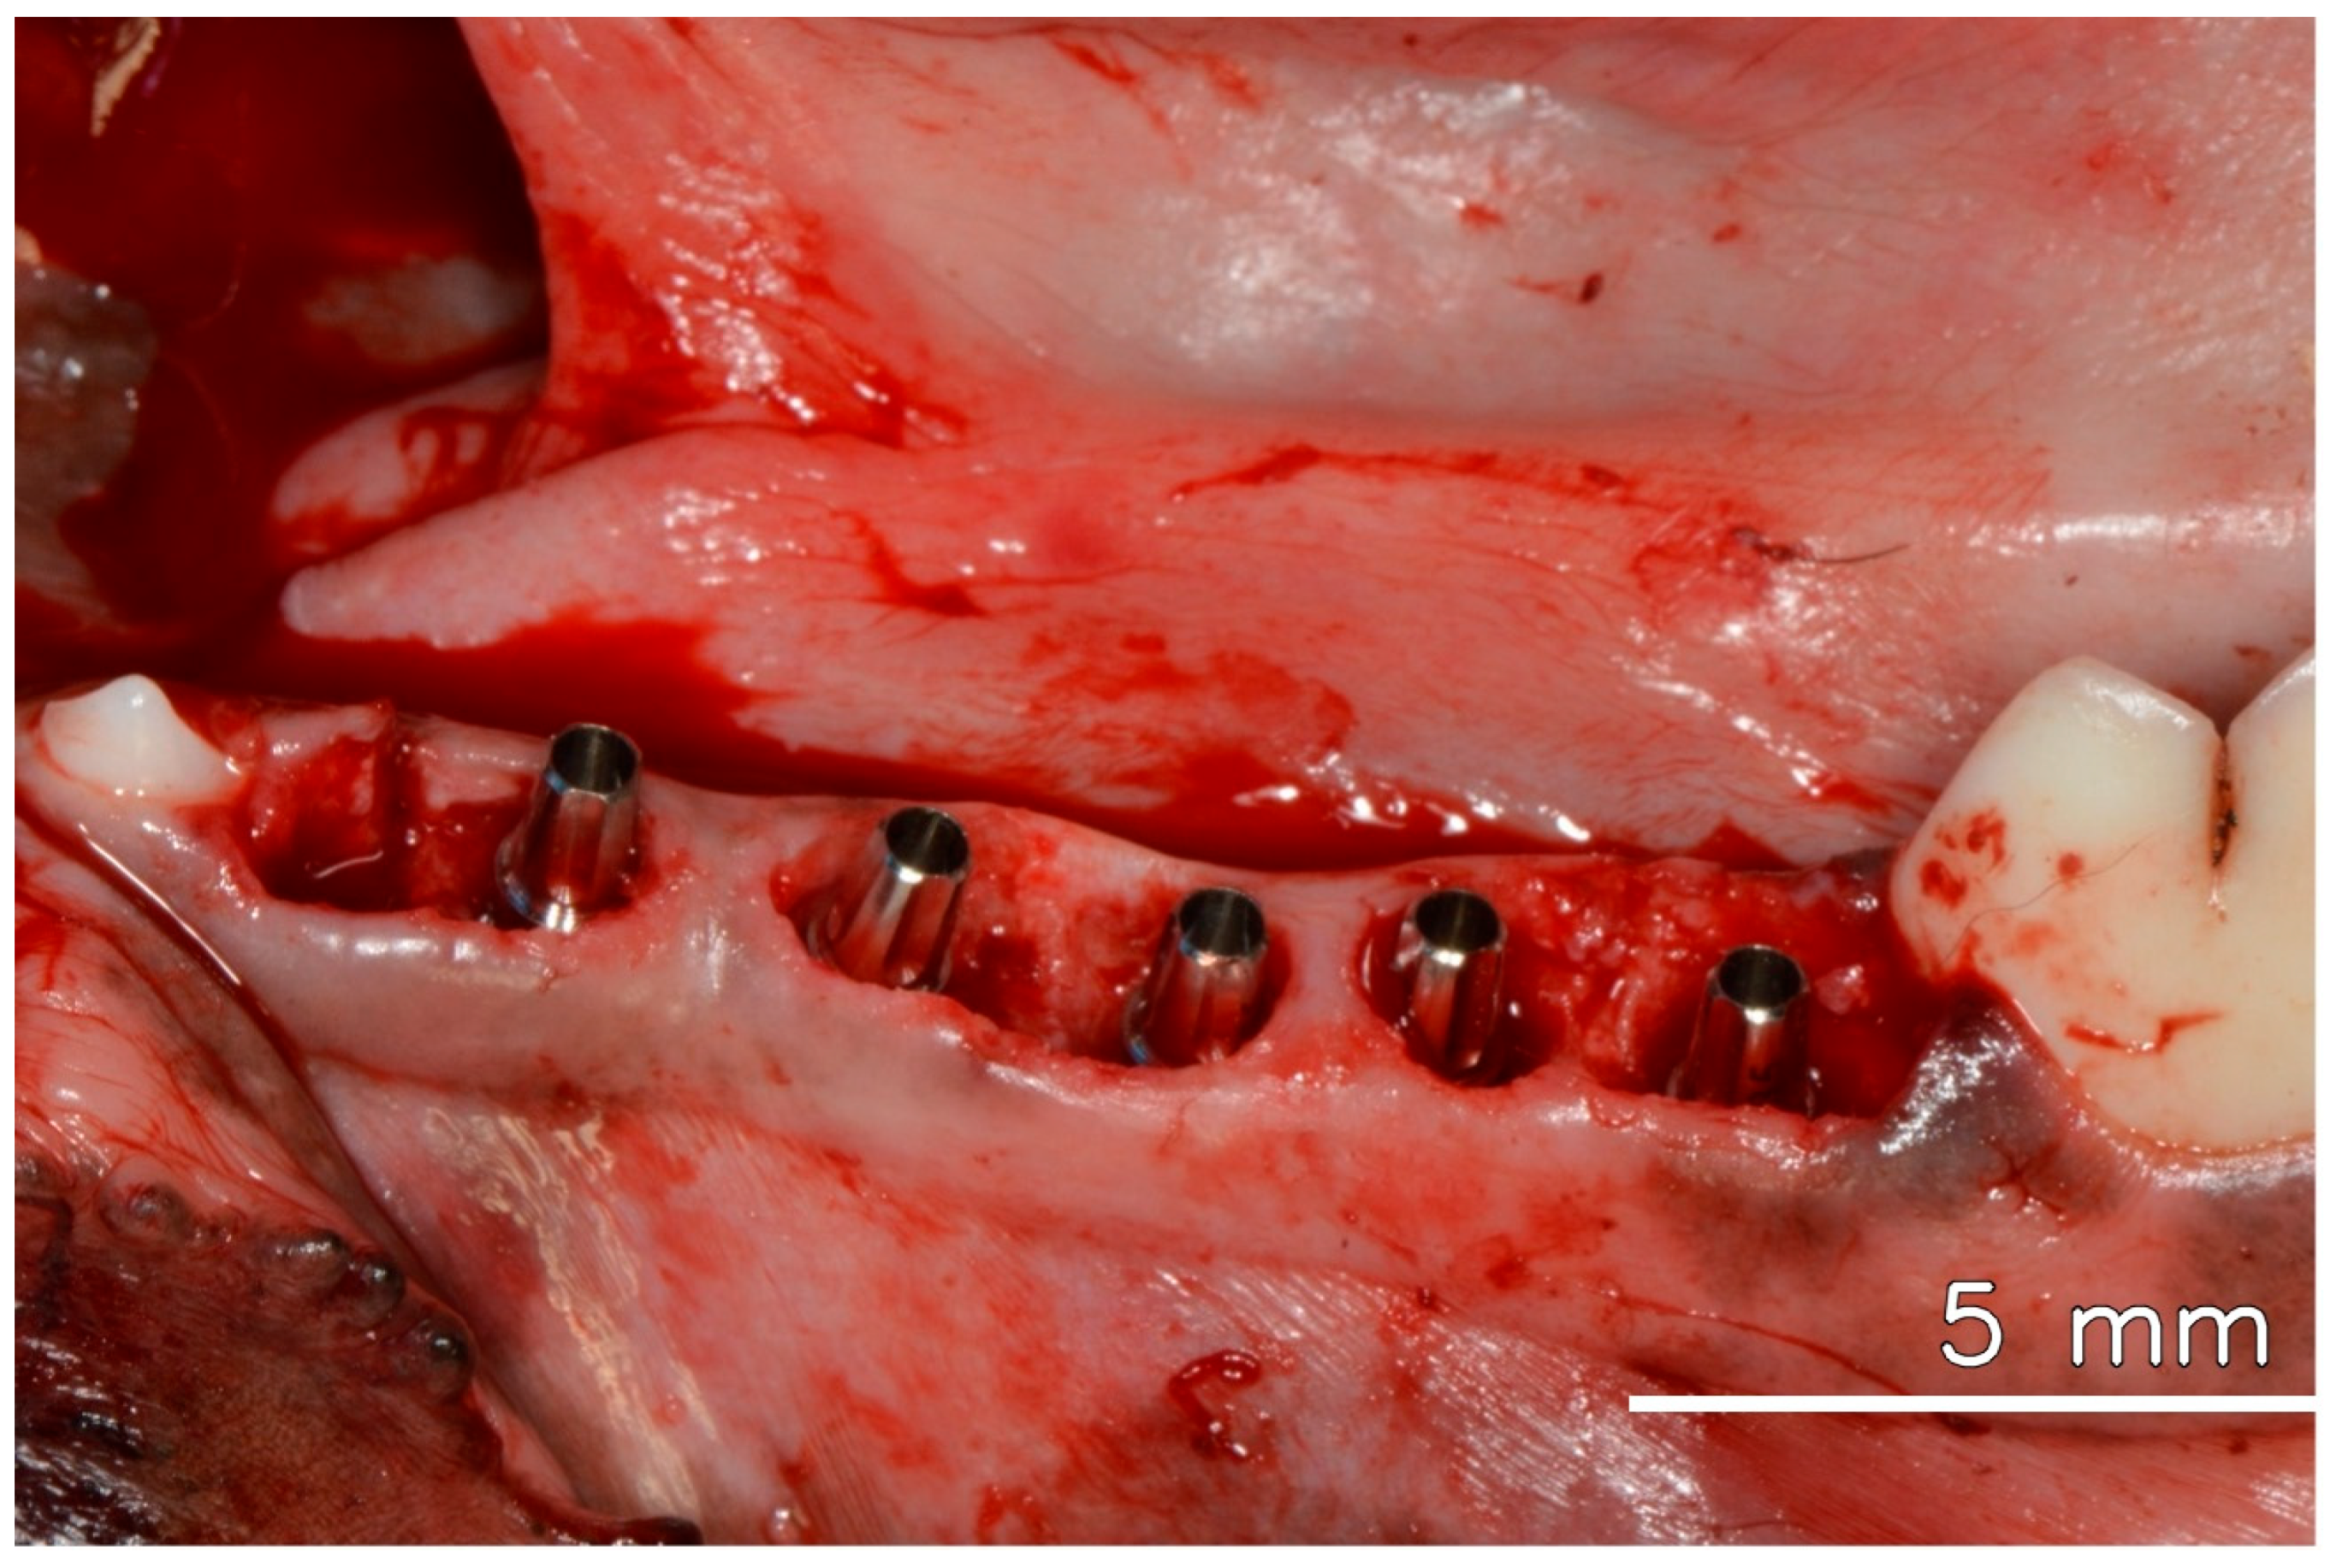

After anesthesia and preparation of the animal, three mandibular premolars were extracted. Five immediate implants, each with a diameter of 3.5 mm and a length of 10 mm, were placed in the extraction sockets and adjacent available areas, all meticulously positioned 2 mm below the bone level. All implants showed stability with an insertion torque of 45 N/cm or higher. Universal abutments (Straumann Neodent GM), with a prosthetic diameter of 3.3 mm, a transgingival height of 2.5 mm, and a prosthetic length of 6 mm, were promptly installed and torqued to 20 N/cm, following the manufacturer’s instructions, which allowed for immediate loading, even without the installation of crowns [2] (see Figure 1).

Figure 1.

Dental implants are installed in the fresh extraction socket immediately after tooth extraction, with their respective abutments.